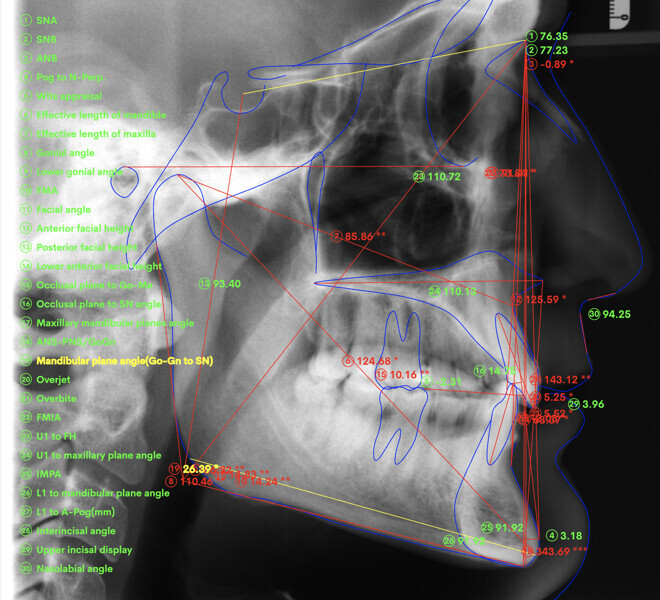

Le motif principal de consultation de ce patient âgé de 37 ans, était de rétablir l’alignement des dents antérieures sur les deux arcades. L’analyse faciale a indiqué une face courte avec un profil plat, mais une projection normale du menton (Figs. 9–12), et l’examen clinique a révélé une classe squelettique de type I (angle ANB = 0,89°) et une malocclusion de classe I avec supraclusion sévère (près de 100 %), une courbe de Spee très prononcée, un torque normal de l’incisive centrale supérieure (Ui-FH = 110°), un encombrement dentaire léger sur l’arcade maxillaire et modéré sur l’arcade mandibulaire (Figs. 13–18). Chez ce patient, les composantes de la supraclusion correspondaient à une dysmorphie squelettique grave correspondant à une hypodivergence (FMA = 14,24°), avec une inclinaison normale des incisives supérieures et inférieures et un angle goniaque réduit (110,46°). L’analyse du cliché céphalométrique indiquait une hauteur réduite de l’étage inférieur de la face associée à l’hypodivergence (Fig. 19). La seule option de traitement envisagée était un traitement orthodontique par aligneurs avec tous les éléments auxiliaires décrits (rampes d’occlusion, zones de pression, nivellement de la courbe de Spee dans les trois dimensions, élastiques de classe II et puissants contacts occlusaux) afin de corriger la supraclusion.

Le plan de traitement numérique (ClinCheck) avait prévu douze aligneurs pour l’arcade maxillaire et dix-sept pour l’arcade mandibulaire. Les objectifs du traitement visaient à combiner les mouvements verticaux d’extrusion des dents postérieures et les mouvements d’intrusion des dents antérieurs, au moyen de rampes d’occlusion, tout en utilisant des taquets d’extrusion pour assurer la désocclusion des dents postérieures et l’intrusion des dents antérieures inférieures, nécessaires au nivellement de l’arcade mandibulaire. La courbe de Spee a été nivelée et le profil plat ainsi que la position des lèvres ont été améliorés par une vestibulo-version des incisives supérieures et inférieures. Le plan avait prévu des élastiques de classe II pour faciliter la vestibulo-version des dents inférieures et les puissants contacts occlusaux postérieurs, avec une extrusion relative des dents postérieures. Une morphologie plus large de l’arcade et une intercuspidation idéale ont été obtenues par des mouvements de torque proches de 0° des dents latérales et postérieures supérieures. Aucune conception technique excessive n’avait été prévue dans le plan de traitement numérique. En raison de l’âge du patient, les aligneurs ont été changés tous les dix jours, dans le cadre d’un traitement d’une durée inférieure à six mois. À la fin de la première série d’aligneurs (Figs. 20–24), un nouveau plan de traitement numérique comportant cinq autres aligneurs a été conçu, en vue d’améliorer l’intercuspidation des molaires sans élastiques. La durée totale du traitement a donc été prolongée jusqu’à 7,5 mois puisque les aligneurs supplémentaires étaient changés toutes les semaines.

À la fin du traitement, on pouvait observer une relation de classe I des canines et des molaires, une légère augmentation de l’inclinaison des incisives supérieures (Ui-FH = 112°), une correction complète de l’inclinaison des incisives inférieures (IMPA = 97,09°) grâce à la vestibulo-version, et une légère amélioration de l’hypodivergence (SN-GoGn = 27°) résultant de l’extrusion relative des dents postérieures, et de l’utilisation d’élastiques de classe II — petite variation (1°) très intéressante compte tenu de l’âge du patient (Figs. 25–35). La ligne du sourire était harmonieuse et correspondait à une relation idéale entre les incisives supérieures et la lèvre inférieure. Le sourire avait été élargi grâce au contrôle du torque des segments latéraux et postérieurs.

La ligne du sourire était harmonieuse et correspondait à une relation idéale entre les incisives supérieures et la lèvre inférieure. Le sourire avait été élargi grâce au contrôle du torque des segments latéraux et postérieurs. La superposition des tracés céphalométriques montrait des changements intéressants induits par le traitement orthodontique (Figs. 36 et 37) :

• L’inclinaison des incisives supérieures était réduite d’environ 2° (de 110° à 112°) par rapport au plan maxillaire, et l’inclinaison des incisives inférieures était réduite d’environ 6° (de 91° à 97°) par rapport au plan mandibulaire. La relation interincisive était satisfaisante et le soutien symphysaire suffisant.

• L’extrusion relative des molaires supérieures et inférieures, combinée avec l’utilisation de rampes d’occlusion, avait mené à une légère rotation de la mandibule dans le sens horaire (SN-GoGn de 26° à 27°), ce qui avait d’autant plus amélioré le recouvrement incisif.

• La vestibulo-version des incisives supérieures et inférieures avait amélioré le profil et le soutien labial.

L’analyse des clichés céphalométriques latéraux superposés du patient à deux dates différentes permet de comparer la ligne verticale du profil et d’évaluer si la correction de la supra- clusion est complète, au moyen d’une combinaison de vestibuloversions prononcées des incisives et une légère rotation mandibulaire dans le sens horaire, induite par l’extrusion relative des dents postérieures.

Les relations squelettiques verticales semblent en outre être influencées par l’utilisation des éléments auxiliaires des aligneurs, puisque les repères céphalométriques verticaux indiquent un changement positif. Chez ce patient, ni intrusion des dents postérieures ni effet de mordu n’ont été constatés à la fin ou au cours du traitement. La modification globale de la position verticale des dents postérieures était minime, mais comme il a été mentionné, la littérature est à l’appui qu’une légère extrusion absolue ou relative des dents postérieures, induite par la biomécanique de l’appareil, peut mener à une ouverture notable de la supraclusion en raison de la rotation dans le sens horaire de la mandibule, ce qui justifie le besoin d’utiliser des rampes d’occlusion qui s’avèrent efficaces en cas de malocclusion de type supraclusion. L’utilisation combinée de ces éléments auxiliaires intégrés dans les aligneurs, d’une minutieuse planification 3D du nivellement de la courbe de Spee, et d’autres auxiliaires, tels que les taquets utilisés pour l’extrusion et la création de zones de pression agissant sur l’arcade mandibulaire, a mené à un meilleur nivellement de la courbe de Spee et à un résultat plus prédictible.